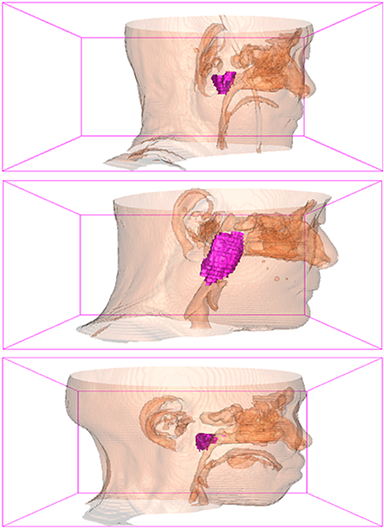

Some typical predicted results of MMFNet are visualized in Figure 12. And it is worth mentioning that our proposed network is extremely time-friendly compared to manually marking by radiologists. Specifically speaking, our proposed method only needs about 9s to realize NPC delineation of a patient, while an experienced radiologist needs 10 to 20 minutes to complete it.

Refer to caption

(a) left view

(b) front view

(c) right view

Figure 12: Some visualization examples of MMFNet’ predicted results, purple regions are NPC regions.